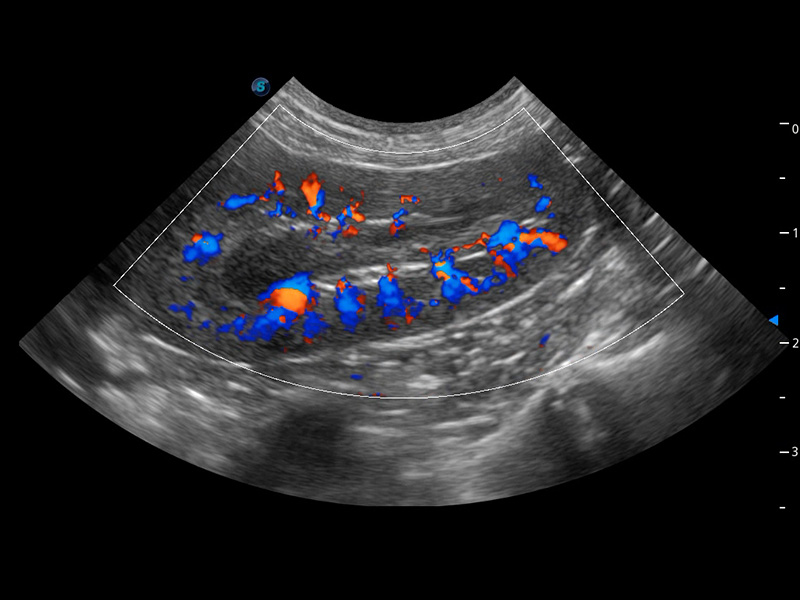

ProPet 60 作为一款高端台式动物超声设备,为动物医生的日常诊断提供了一系列贴合动物临床需求、解决临床实际问题的高级成像功能。凭借全系列高清探头,满足医生对腹部、心脏、生殖、浅表、肌骨等成像的所有需求,切实帮助您提升检查效率,提高诊断信心。

动物是人类最亲密的朋友和最值得信赖的伙伴。db真人体育官网也一直致力于探索动物专用的超声影像解决方案。 全新推出的ProPet系列,是db真人体育官网在动物超声影像智能化、专业化、精准化的一次跨越式革新。动物不能用言语来表述自己的不适,通过超声影像,ProPet系列搭建了动物医生与不同物种沟通的“桥梁”,为动物医生注入了“治愈之力”。